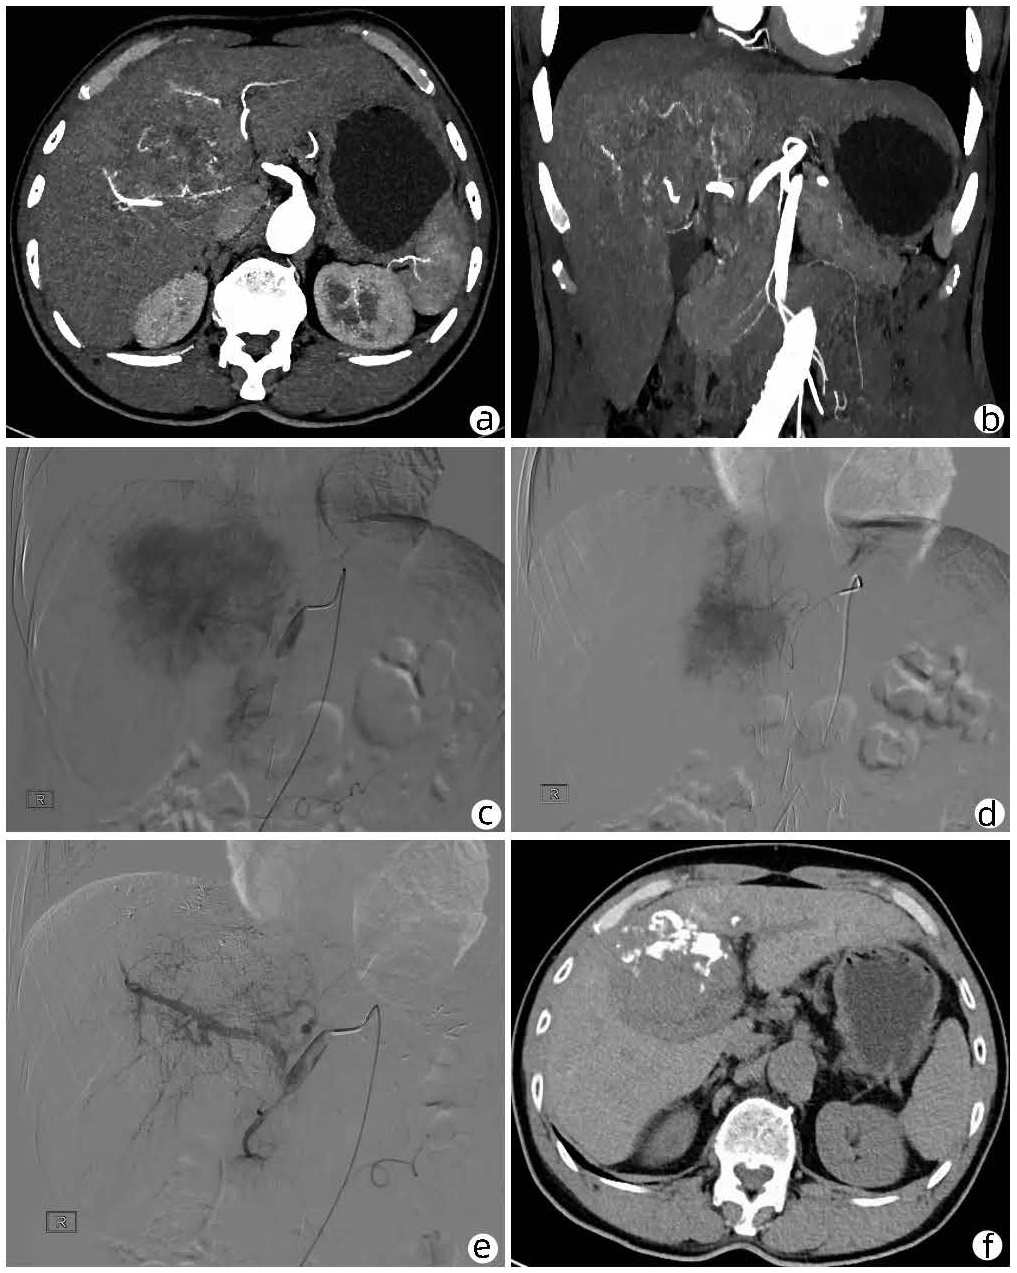

局部栓塞联合靶向免疫综合治疗肝肉瘤样癌1例报告

雷进, 张林枝, 陆荫英, 陈博文, 左石

2022, 38(4): 880-882. DOI: 10.3969/j.issn.1001-5256.2022.04.026

摘要(1328) HTML (453) PDF (3487KB)(83)

摘要: